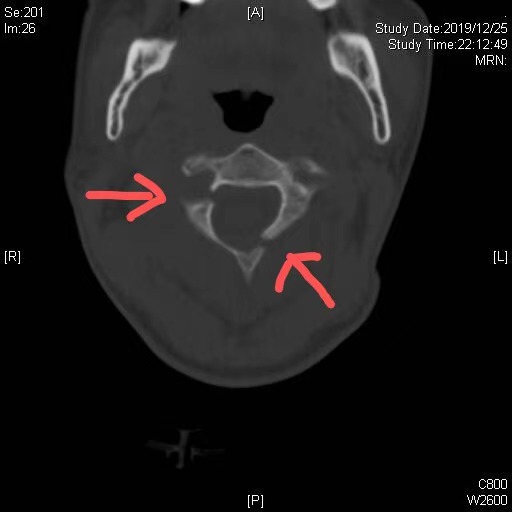

患者刚过知天命之年,车祸导致其第二颈椎(枢椎)多发骨折,骨科肖嵩华主任医师评估患者情况后,认为该骨折累及枢椎的椎弓根、椎板及附件,属于不稳定性骨折,具备内固定的手术指征,然而该患者损伤部位较高,紧邻生命中枢,且骨折块细小,对螺钉置入的精度要求极高(误差容错小于1mm),手术难度较大。“如果采用传统的手术方式,手术需要从颈后部位开大口子,创伤较大,对患者的恢复不利。”胡冬医师说道。为使患者能够更快康复,肖嵩华决定使用天玑机器人为患者进行手术。

患者骨折影像图,箭头部位为骨折位置